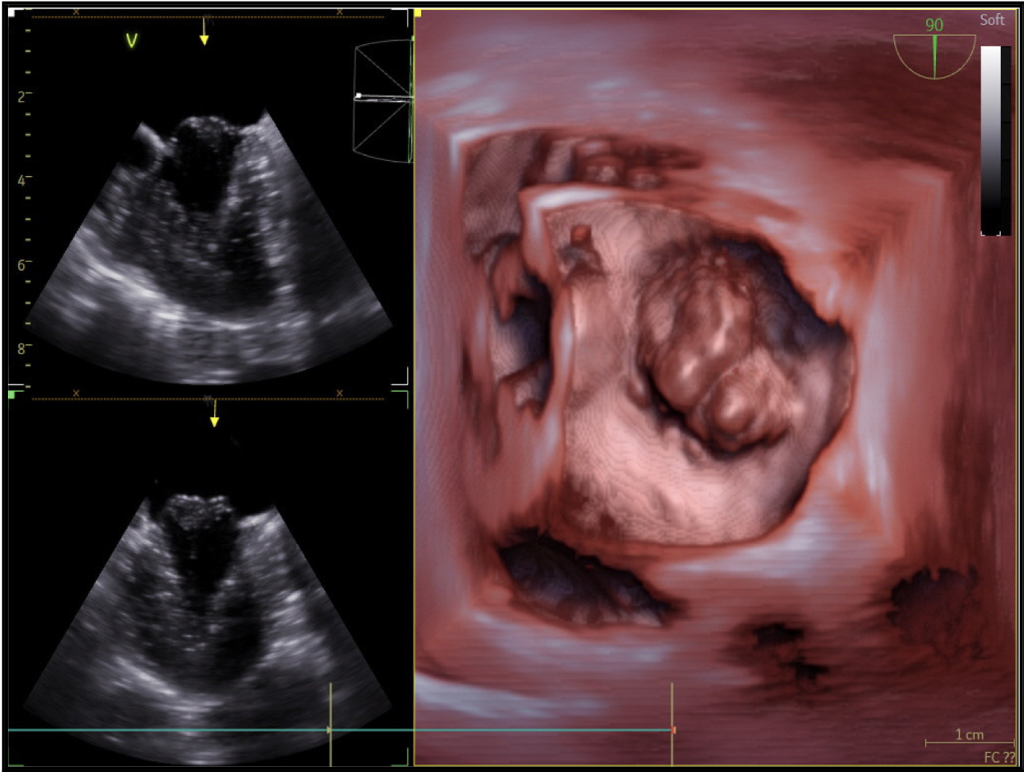

Échographies cardiaques transœsophagiennes

(2 sondes : PÉDIATRIQUE + ADULTE 4D)

L’échographie par voie transœsophagienne (ETO) a l’avantage, par rapport à l’échographie transthoracique (ETT), de contourner la cage thoracique et les poumons, pour aborder directement le cœur et obtenir une haute définition des images. Une sonde ultrasonore est montée sur un fibroscope flexible et introduite dans l’œsophage de l’animal sous anesthésie générale. La sonde endoscopique est directement raccordée à l’échographe.

Les applications pratiques spécifiques de l’ETO concernent surtout :

- l’évaluation précise des maladies valvulaires (insuffisance mitrale en particulier) pendant les chirurgies cardiaques

- l’exploration des endocardites

- la détection de masses et de tumeurs intra- et extracardiaques

- l’étude plus précise des shunts intracardiaques, pendant la chirurgie correctrice ou bien lors du diagnostic de maladies congénitales

- l’étude de la fonction ventriculaire gauche pendant et après les chirurgies cardiaques (contractilité, volume sanguin…)

Technologies additionnelles disponibles à HOPia :

Echographie 4D, Doppler tissulaire, Strain, Speckle Tracking Imaging, Echographie trans-oesophagienne 4D, Logiciel de reconstruction de la valve mitrale